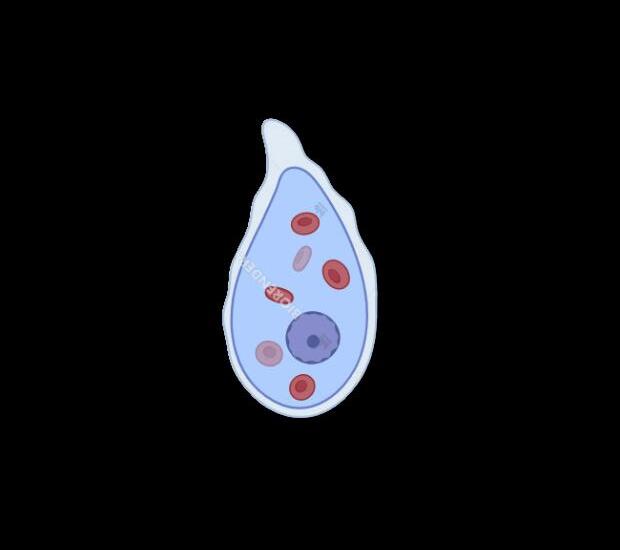

TROFOZOITO

Microorganismo piriform

Fluctúa entre 10 y 60 m

Posee un núcleo con cr periférica

Posee un forma variable

Se observa en el endop

El núcleo es esférico

Presenta cariosoma cen

QUISTE

Forma esférica u oval.

Mide de 10 a 15 µm.

De forma redondeada y

Contiene de 1 a 4 núcleos, dependiendo de la madurez del quiste.

se pueden observar vacuolas, el núcleo, dos cuerpos cromatoides y la pared del quiste.